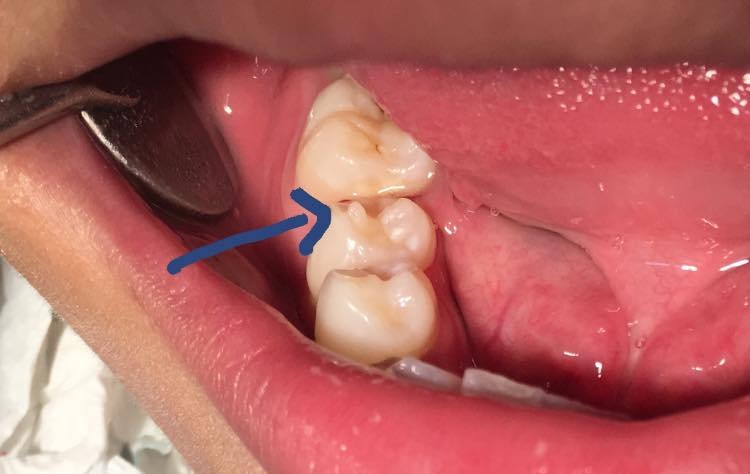

Núm phụ răng (Dens evaginatus) là thuật ngữ được dùng để chỉ những bất thường của răng có hình dạng giống như núm, múi dư trên bề mặt răng. Tình trạng này thường xuất hiện ở mặt trong của răng hàm trên (Còn gọi là múi Talon) hoặc mặt nhai của răng cối nhỏ hàm dưới.

Núm phụ trên răng này có cấu tạo tương tự như răng bình thường với men răng, ngà răng và tủy răng. Nhưng núm phụ này nhô lên dẫn đến mô tủy ở đó cũng nhô lên theo tạo thành những sừng tủy mảnh. Mô tủy này có nguy cơ bị bộc lộ trong quá trình ăn nhai do mài mòn hoặc do lực nhai dồn xuống vị trí này quá mạnh dẫn đến các biến chứng như hoại tử tủy, áp xe quanh chóp và thường xuất hiện sớm khi chân răng chưa hình thành hoàn chỉnh.

Sự có mặt của tủy trong núm phụ này có ý nghĩa trên lâm sàng rất quan trọng và việc nhô lên của sừng tủy là cách phân biệt với các núm bổ sung (Núm Carabelli).